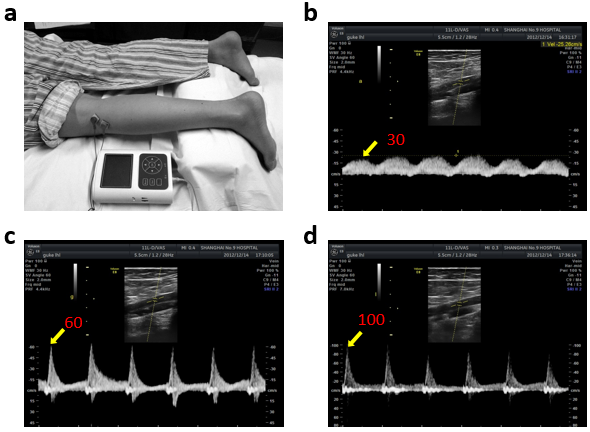

可穿戴式预防深静脉血栓的智能经皮神经电刺激器是一款针对深静脉血栓(DEEP VEIN THROMBOSIS,DVT)的医疗器械产品,具有最佳电刺激参数、小型化、智能化的优势,体积小巧,使用时方便有效,已经完成的志愿者实验证实可以提高患者腘静脉峰值血流速度8倍,与传统方法相比有着压倒性的竞争优势。目前国内尚无针对DVT的同类产品,本产品系自主研制,价格上有着很大的竞争优势。 深静脉血栓(DEEP VEIN THROMBOSIS,DVT)是围手术期常见的并发症,其导致的静脉瓣膜功能不全会使患者肢体残疾,并发的肺栓塞危及患者生命。在关节置换手术中,亚洲人群DVT的发病率为43.2%,近年来还在不断增加。目前我国73.3%的医院已开始制定深静脉血栓预防的护理规范。该病重在预防,医护人员需要协助患者做床上运动,让腿部肌肉收缩,从而挤压附着在肌肉上的静脉,促进血液回流。本产品是一种小型贴附式的功能性电刺激器,使用时只需贴附于腓总神经处即可令腿部肌肉主动收缩,促进静脉回流,极大地减轻医护人员负担。 目前针对深静脉血栓的防治方法均存在诸多不足。抗凝药副作用大,会增加服药者的出血风险。常用的梯度压力弹力袜和间歇充气加压两种物理预防方法,患者顺从性差,且机械力难以作用于深层静脉。 考虑到传统预防方法的严重不足,课题组不断寻找新的物理防栓方法。最终发现通过使用特定参数的电脉冲刺激腓总神经可以显著增强下肢静脉血液回流,进而预防深静脉血栓。

目标客户: 1)医院内手术后康复期患者 骨科手术后静脉血栓患病率为40%--60%,血栓一旦脱落随血液流动进入肺中会引起患者死亡。目前临床上在完成手术后直接给患者注射适量的华法林等抗凝药预防血栓。但药物预防存在诸多严重的不良反应,患者需要使用物理方法促进静脉血液回流,尽早摆脱抗凝药物。 本项目针对手术后患者,即为一种新式的物理预防静脉血栓手段,前期的志愿者实验证实了对志愿者下肢腘静脉内血流速度增加效果约为原来的3.5倍(平均血流量)。在注册CFDA认证后即可通过现有的医疗代理公司销往医院,作为正规的医疗器械供广大患者使用。 2)长期卧床、久坐等亚健康高危人群 癌症患者的静脉血栓发病率约为15%,妊娠期、产后妇女也为静脉血栓高危人群。长期卧床者,尤其是老年人,静脉血栓发病率非常之高。据统计,在欧洲每年有超过50万人死于该病,在美国,每年有10-30万人死于静脉血栓。 3)长途飞机、长途汽车旅客 下肢深静脉血栓曾被称为“经济舱综合征”。已故美国前总统尼克松,1974年乘飞机对欧洲、中东和苏联进行访问,长时间的空中旅行,使左下肢深静脉血栓形成,虽在机上及时进行抗凝治疗,终究还是发生了肺栓塞,后经治疗方脱离危险。长途飞机、长途汽车旅客由于座位空间狭小,活动不便,很容易形成静脉血栓。 相关媒体文章 A.得过深静脉血栓还能坐飞机吗? HTTP://WWW.HAODF.COM/ZHUANJIAGUANDIAN/ZHOUMIDOC_3149886807.HTM B. 静脉血栓就藏在我们身边(组图) HTTP://NEWS.163.COM/15/0129/11/AH4G875J00014AED.HTML C. 深静脉血栓成经常久坐者可怕杀手 HTTP://HEALTH.ZJOL.COM.CN/05ZJHEALTH/SYSTEM/2012/12/27/019048421.SHTML D. 专家:久坐会引起静脉血栓 伏案工作者是高危人群 HTTP://MONEY.163.COM/15/0608/10/ARJ53PM300254TI5.HTML